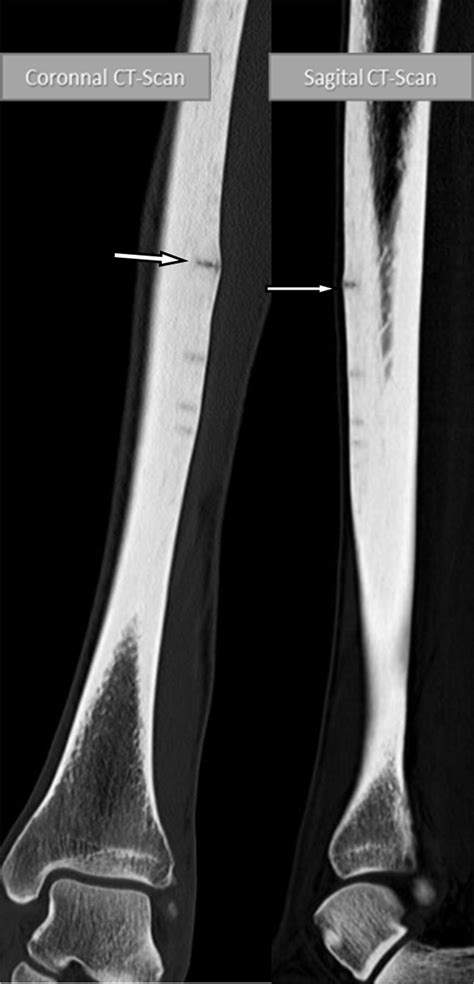

If you suspect you have a stress fracture, it is vital to seek professional medical advice. A healthcare provider will typically perform a physical examination, assessing the site of tenderness and your range of motion. Because stress fractures are often so small, they do not always appear on standard X-rays, especially in the first few weeks of the injury.

Doctors may suggest more sensitive imaging techniques if clinical symptoms remain high despite a clear X-ray. An MRI is often considered the "gold standard" for diagnosing a stress fracture tibia because it can detect bone marrow edema (swelling inside the bone), which is an early sign of stress-related injury before a fracture line even forms.